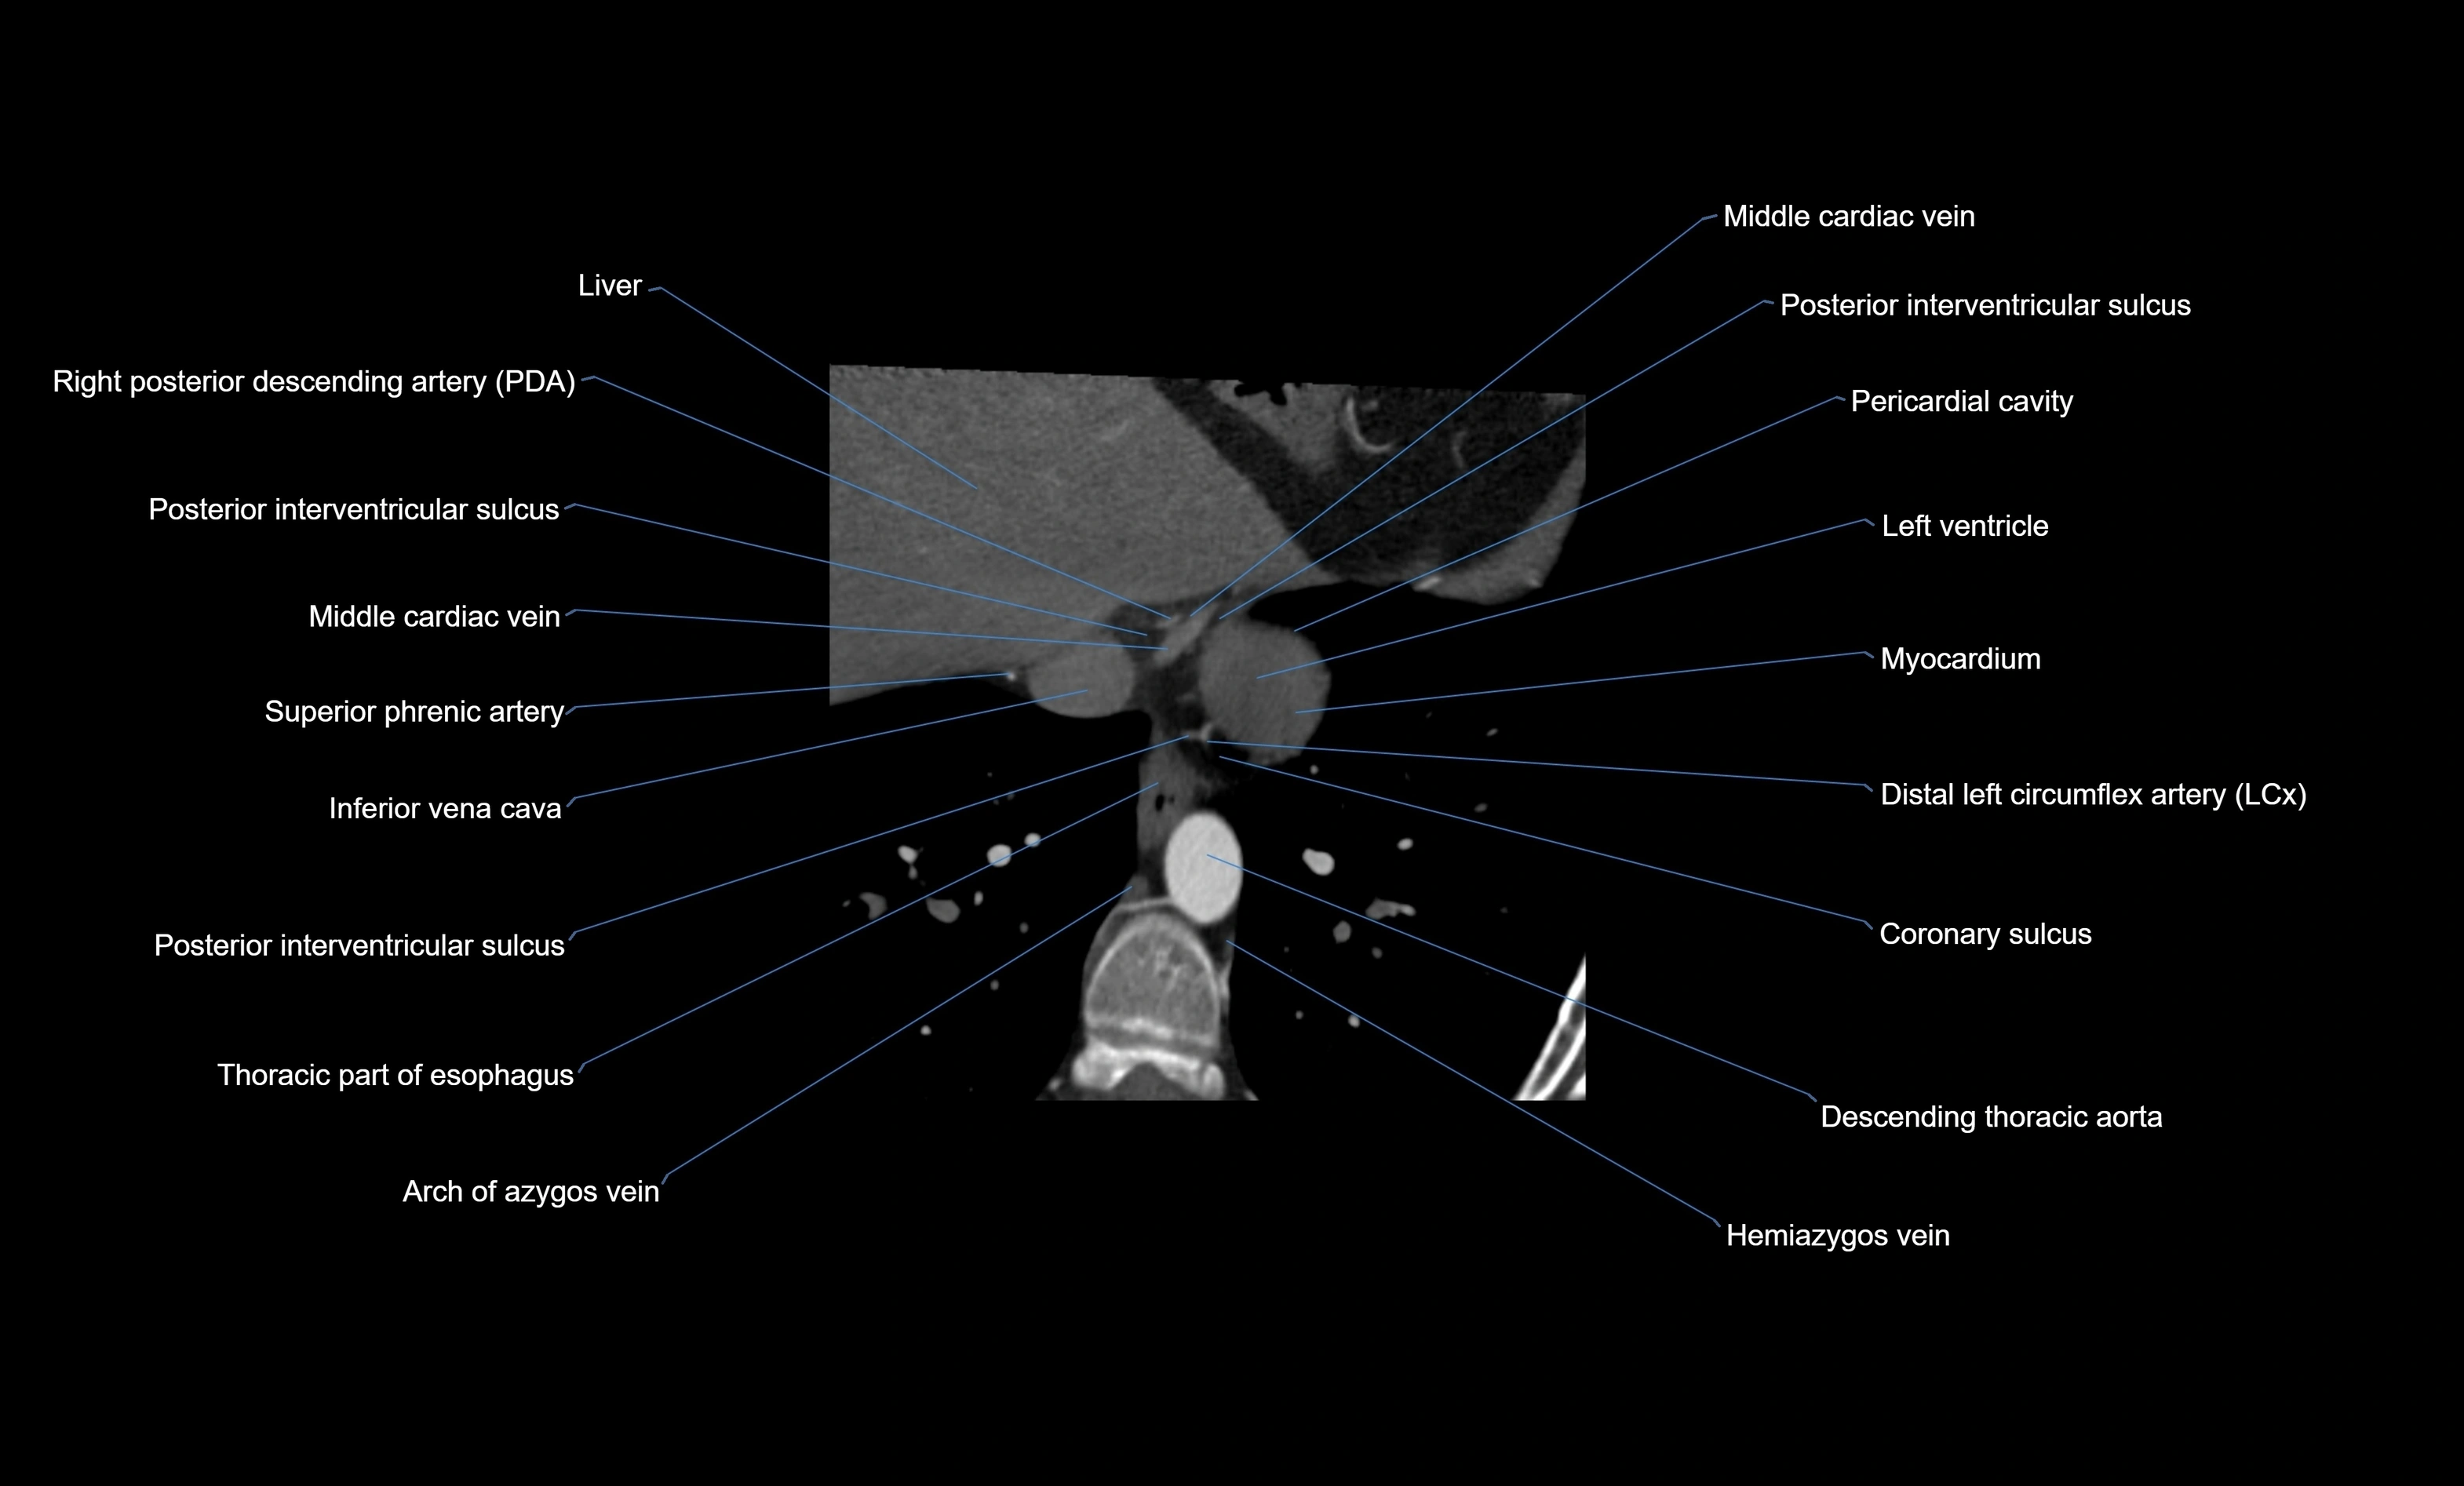

- Middle cardiac vein

- Posterior interventricular sulcus

- Pericardial cavity

- Left ventricle

- Myocardium

- Right posterior descending coronary artery (Right PDA)

- Inferior vena cava

- Descending thoracic aorta

- Posterior intercostal veins

- Posterior intercostal arteries

- Azygos vein